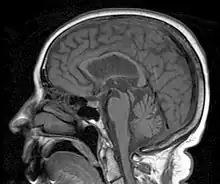

L'IRM cérébrale peut révéler quelques anomalies caractéristiques : amincissement de la partie supérieure de la protubérance (coupe sagittale), écartement des pédoncules cérébraux (coupe axiale), élargissement du 4e ventricule (coupe axiale), atrophie frontale.

Mésencéphale et rhombencéphale (vue postero-latérale).